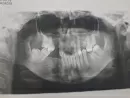

Какой в моем случае по снимку вид протезирования будет лучшим?

Только что вышла от ортопеда, хотела установить несъемный протез. Врач говорит, что судьба моя печальна — либо съемный протез, либо имплантация.

Не очень доверяю, так как в данной поликлинике с недавних пор появилась эта услуга и есть мнение, что стоматологи раскручивают так сказать на эту услугу.

Прав ли врач?

По данному снимку, доктор прав. Лучшим вариантом лечения будет имплантация зубов, так как это наиболее современный метод протезирования, надежный и долговечный.

Возможно, что на нижнюю челюсть получится установить мостовидный протез — несъёмную конструкцию. Но необходим осмотр.

Очно проконсультируйтесь с другим специалистом, стоматологом-ортопедом.